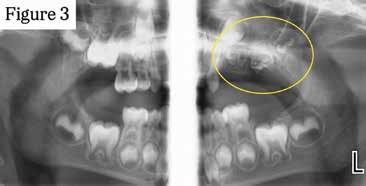

earn up to 6 hours of general continuing education (CE) by reading the Diagnostic Discussion column included in the bi-monthly Today’s FDA and taking a quick online quiz